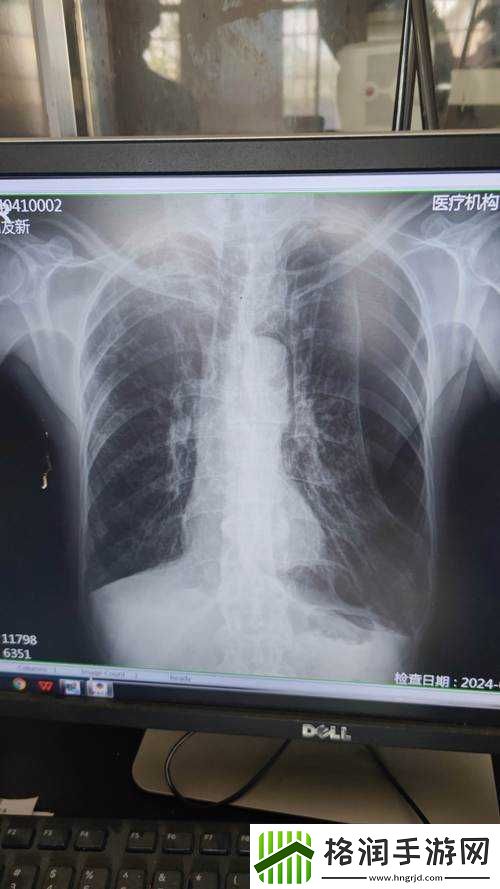

这张看似普通的图片,却蕴含着无尽的秘密与挑战。它让我们直面医疗过程中那些可能被忽视或隐藏的问题。曝光度达到 100%,意味着什么?是技术上的失误,还是隐藏着某些不为人知的医疗状况?

从技术层面来看,如此高的曝光度可能是由于设备故障、操作不当或者其他原因导致的。这就要求医疗团队不断提升自身的专业技能,熟悉各种设备的性能和操作规范,以确保影像质量的准确性。定期的设备维护和校准也是不可或缺的环节,不能让任何一个潜在的隐患影响到医疗诊断的准确性。